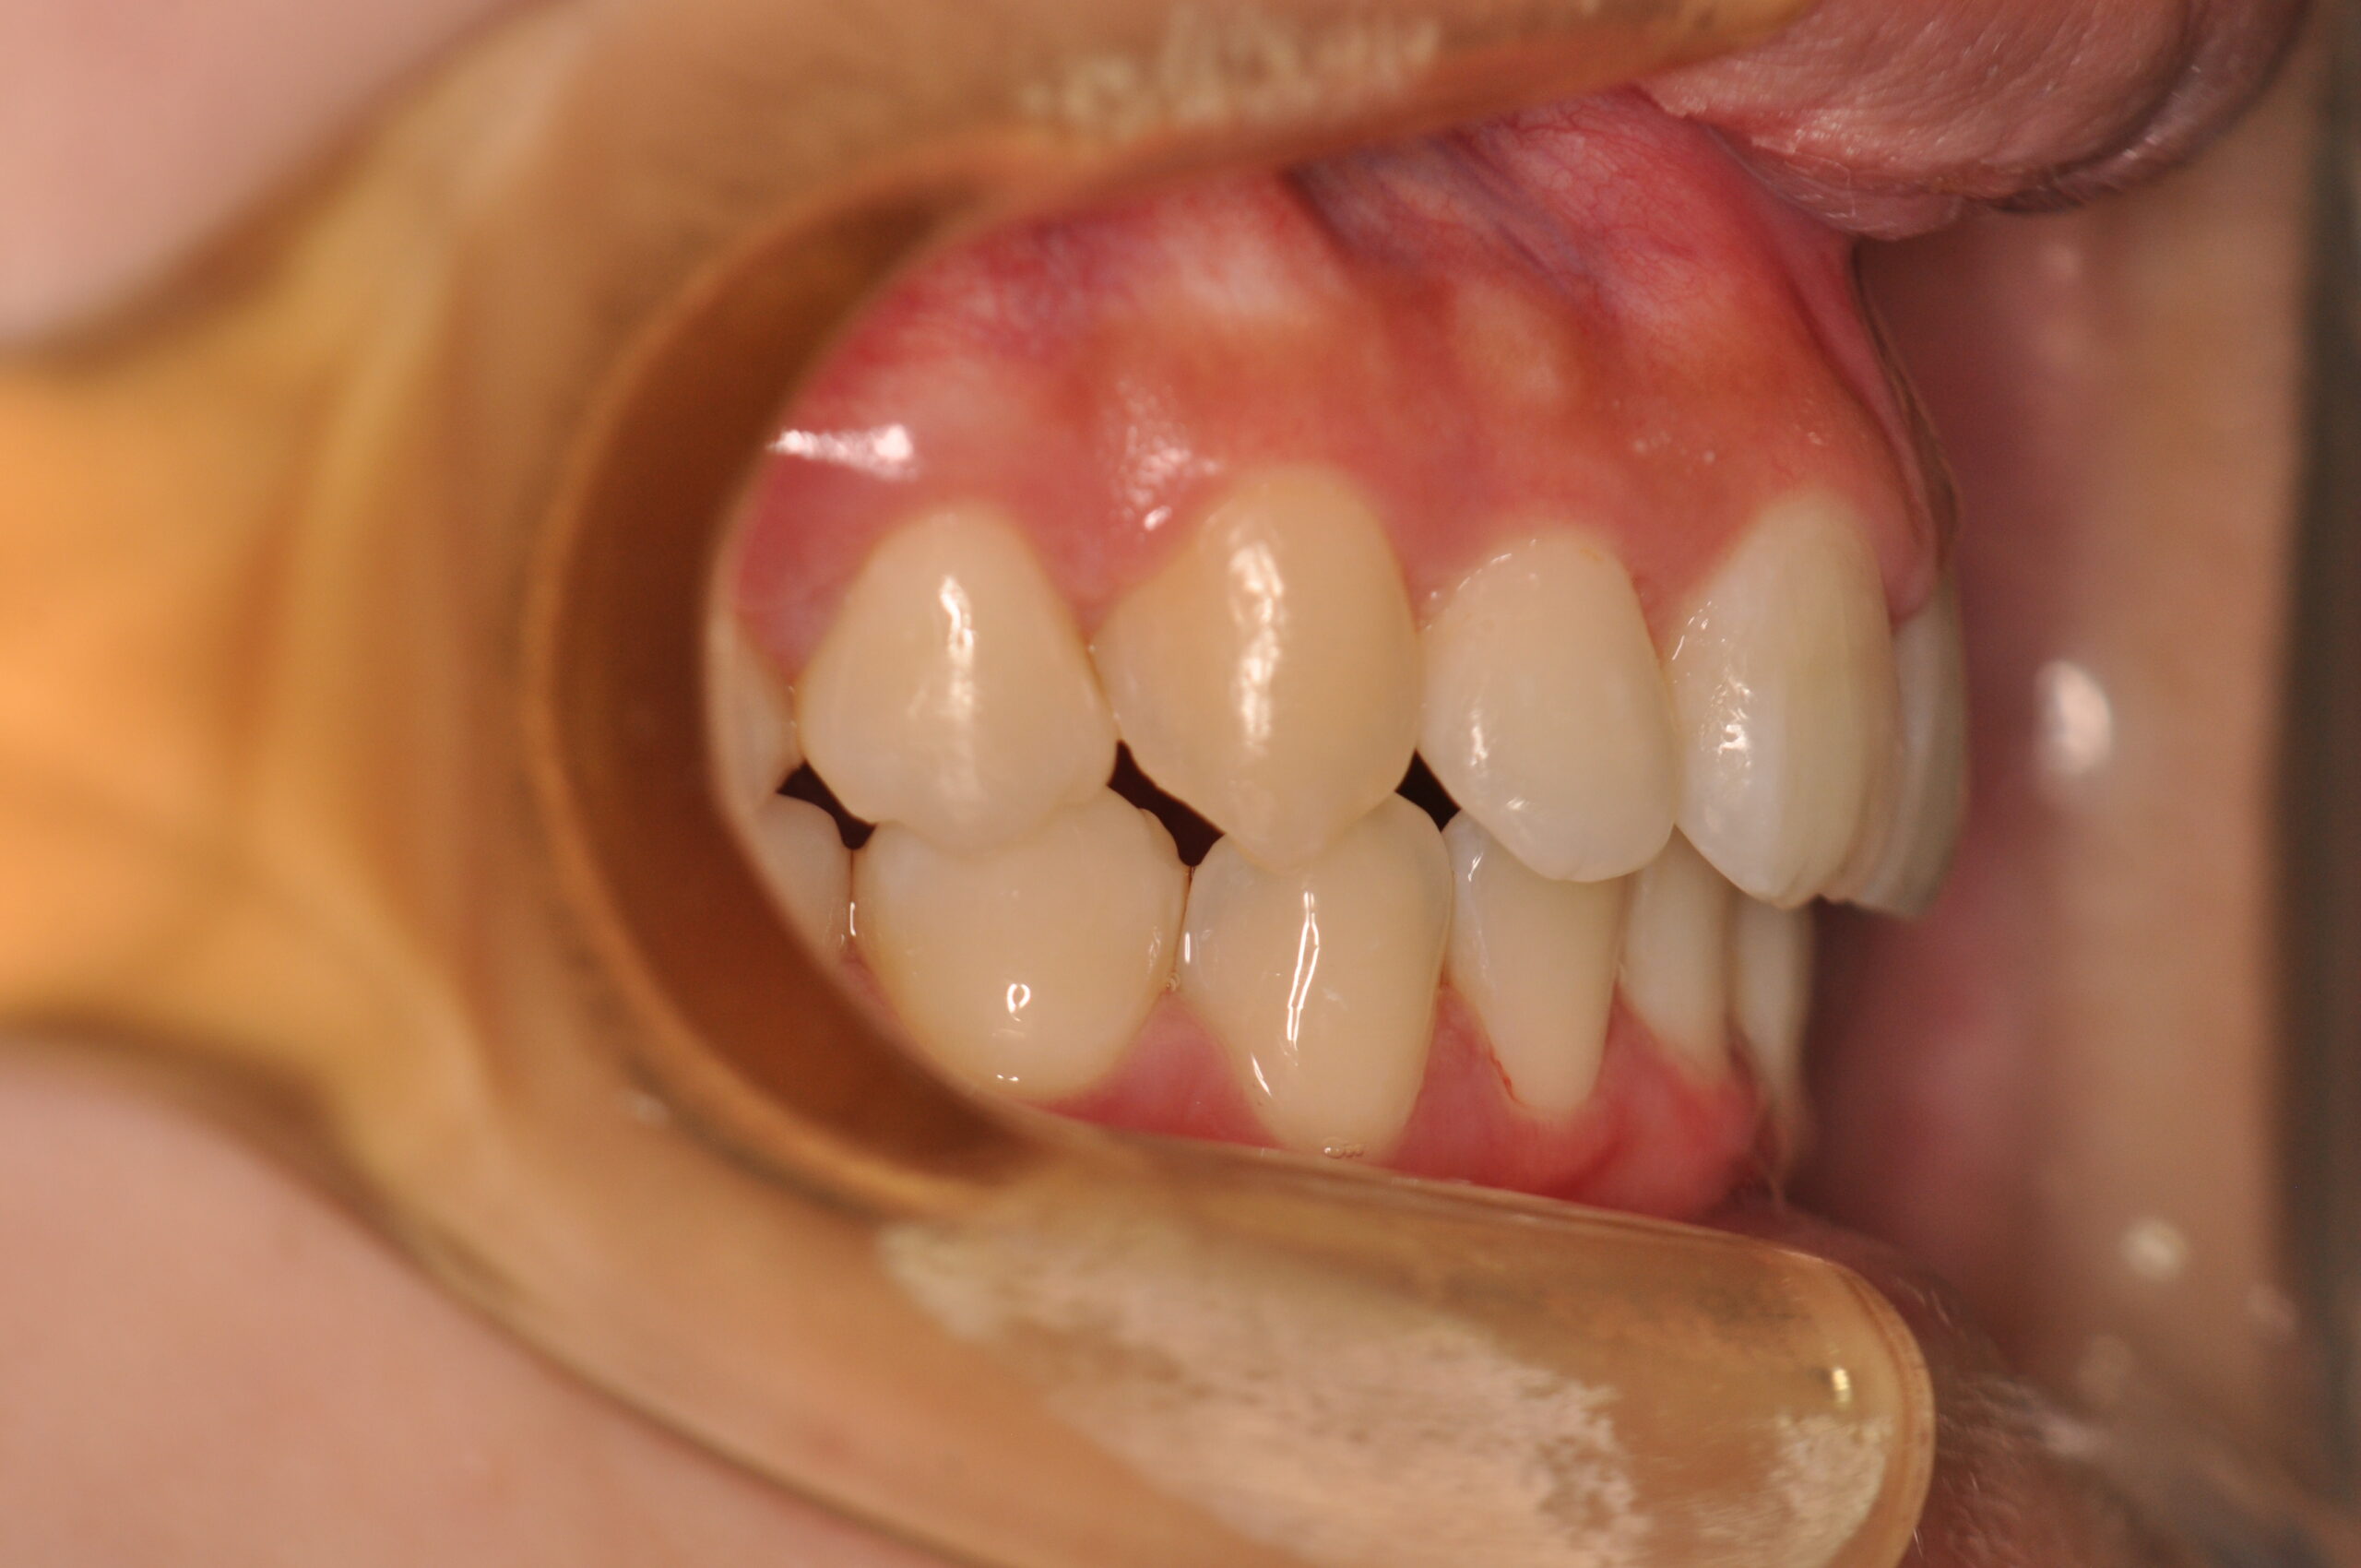

動的治療終了時

症例 症例 症例 症例 症例